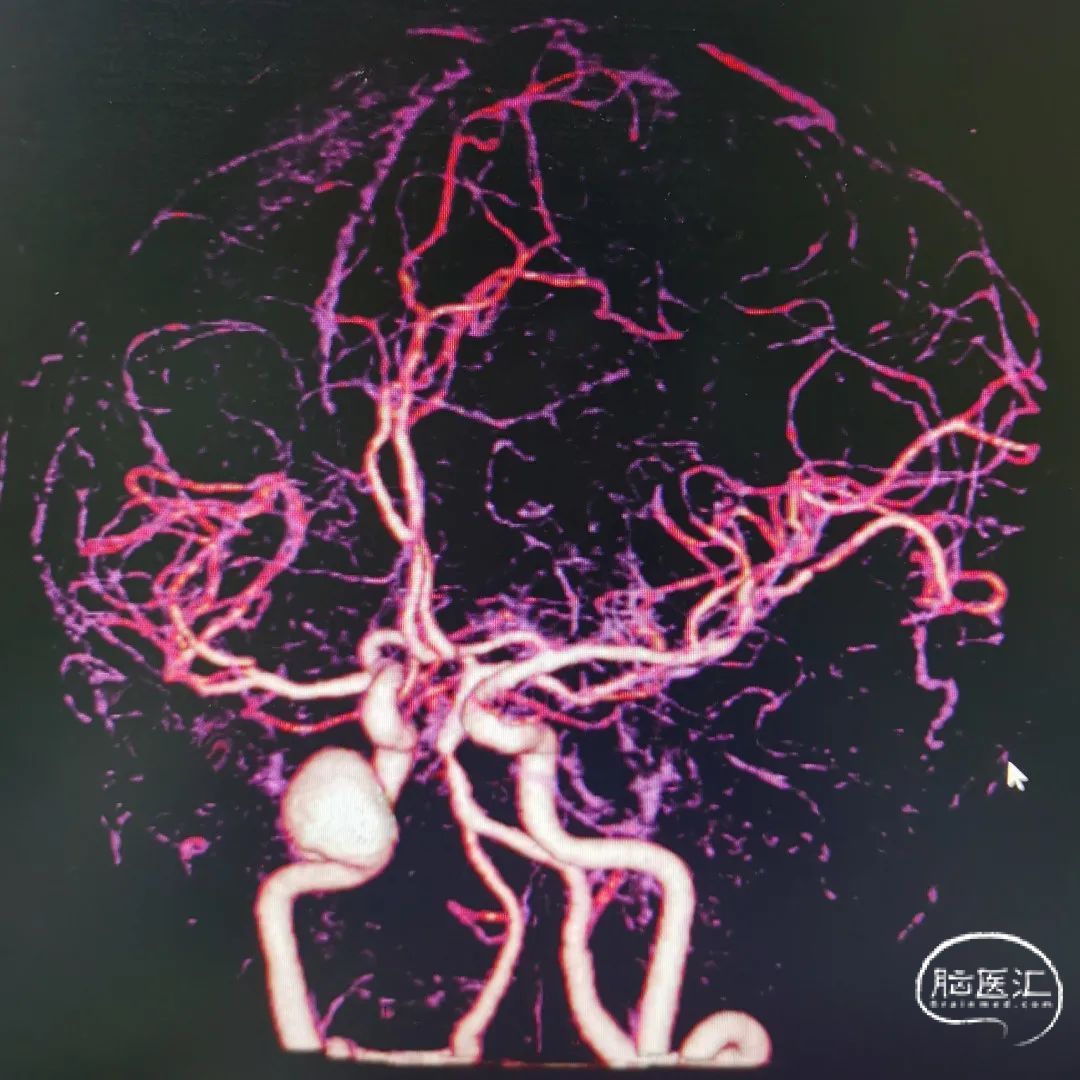

图2 头颅CTA提示右颈内末端动脉瘤,前交通动脉瘤

右颈内动脉交通段以远瘤样扩张,钙化明显,载瘤动脉完全瘤化,局部可见多处小阜突起,无明显瘤颈,最大约16mm╳11mm,前交通囊状动脉瘤约4mm╳3mm,瘤颈约4mm。